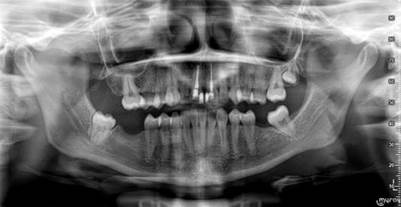

Estudios complementarios

Radiografías panorámicas y periapicales: Se observan crestas óseas normales, inclinación de piezas dentales por falta de piezas adyacentes, en la pieza 11 se indica realizar retratamiento de conducto. El resultado de la radiografía panorámica se observa en la figura 4.

Figura 4 Radiografía panorámica.